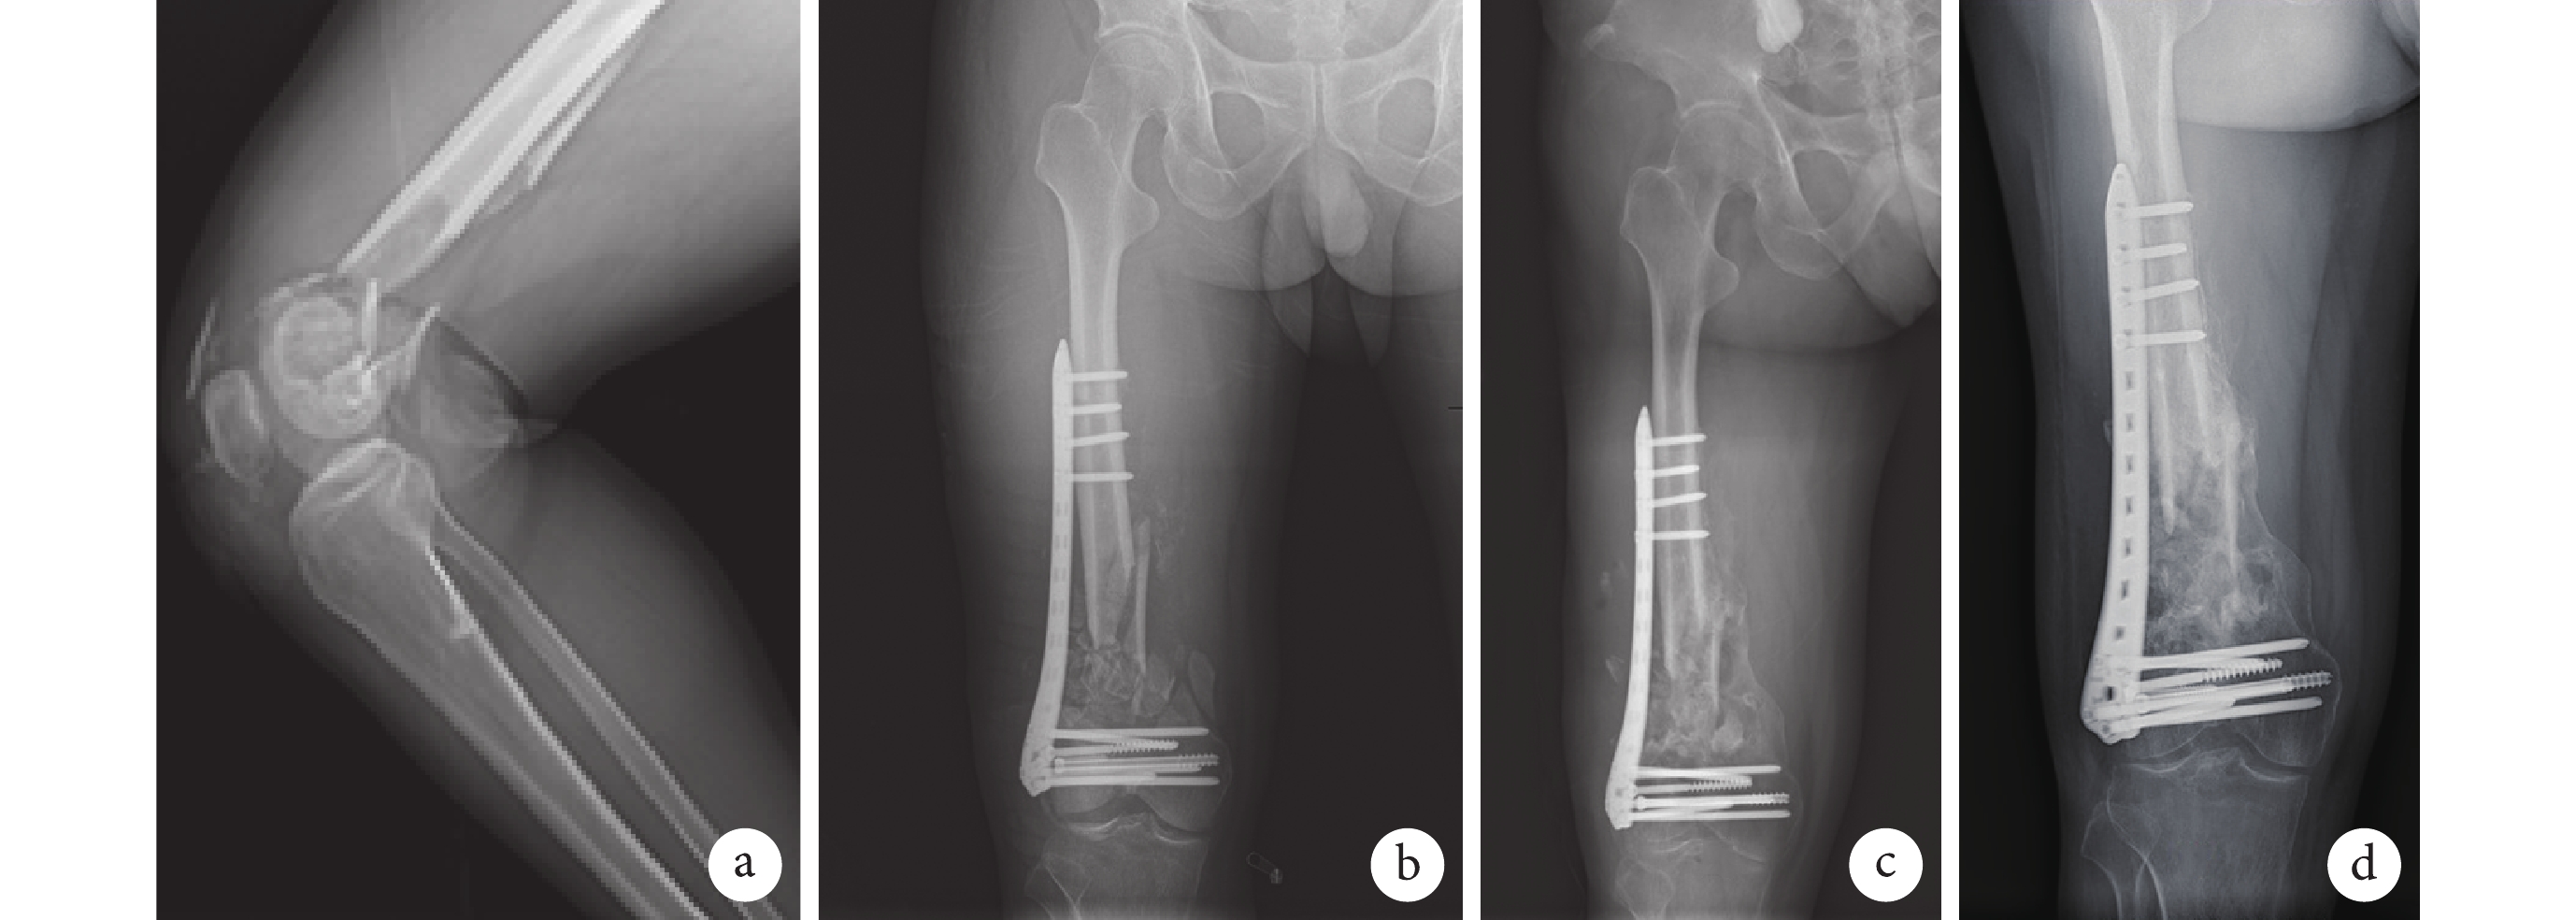

a. 術前;b. 術后第 3 天;c. 術后 3 個月;d. 術后 5 個月

Figure2. X-ray films of a 38-year-old male patient with right distal femoral type C3 fracturea. Before operation; b. At 3 days after operation; c. At 3 months after operation; d. At 5 months after operation

兩組均順利完成手術,術中均無重要神經血管損傷。改良組手術時間較傳統組明顯延長,術中透視次數增加,失血量減少,差異均有統計學意義(P<0.05);兩組住院時間差異無統計學意義(t=0.277,P=0.783)。見表 1。兩組患者均獲隨訪,隨訪時間 6~8 個月,平均 7.2 個月。兩組骨折均愈合,愈合時間差異無統計學意義(t=0.861,P=0.394)。見表 1。傳統組 12 例、改良組 10 例患者于骨折愈合后取出內固定物。患者術后關節功能均逐漸恢復,改良組術后 3、6 個月 HSS 評分分別為(82.91±2.88)、(89.28±3.63)分,均優于傳統組的(74.62±3.64)、(81.48±4.55)分,差異均有統計學意義(t=8.306,P=0.000;t=6.231,P=0.000)。見圖 2。